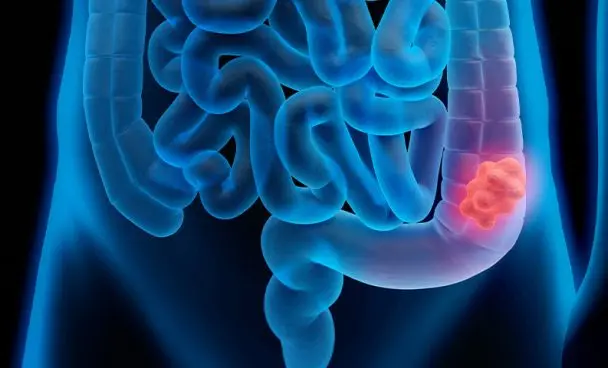

O câncer colorretal é uma das neoplasias mais comuns no Brasil e no mundo, mas pouca gente sabe que sua localização influencia diretamente nos sintomas que aparecem. O tumor de cólon direito, por exemplo, costuma apresentar sinais diferentes dos tumores do cólon esquerdo ou do reto — e, justamente por isso, é mais difícil de detectar precocemente.

O cólon faz parte do intestino grosso e é dividido em segmentos. O cólon direito compreende a porção inicial do intestino grosso: o ceco, o cólon ascendente e a flexura hepática. Essa região é responsável pela absorção de líquidos e pela formação inicial das fezes.

Os tumores que surgem ali pertencem ao grupo dos cânceres de intestino e têm características clínicas e biológicas distintas dos tumores do lado esquerdo, o que influencia no padrão de sintomas e na forma como são detectados.

Uma das grandes particularidades do tumor de cólon direito é o seu caráter silencioso. Isso acontece porque as fezes ainda estão líquidas nessa parte do intestino, o que impede o surgimento precoce de sintomas como obstrução intestinal ou sangue visível nas evacuações.